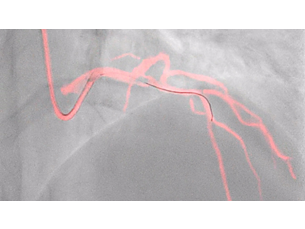

Achieve low dose and excellent visibility with an AlluraClarity upgrade. Extend the life of your interventional lab with a Catalyst conversion or enable advanced procedures in interventional radiology, cardiology, neuroradiology, and oncology with Live Image Guidance tools.

During interventions you want to see with confidence – every time. AlluraClarity with ClarityIQ allows you to do this at low dose. In fact, from 18 peer-reviewed clinical studies with 3840 patients, comes one truth – you can achieve significantly lower dose across clinical areas, patients, and operators* using this technology.

Our Live Image Guidance tools and wide screen technology help enable advanced procedures through intelligent and intuitive integration of multi-modality images at the point of treatment, helping physicians make confident diagnoses and enabling real-time therapy monitoring.